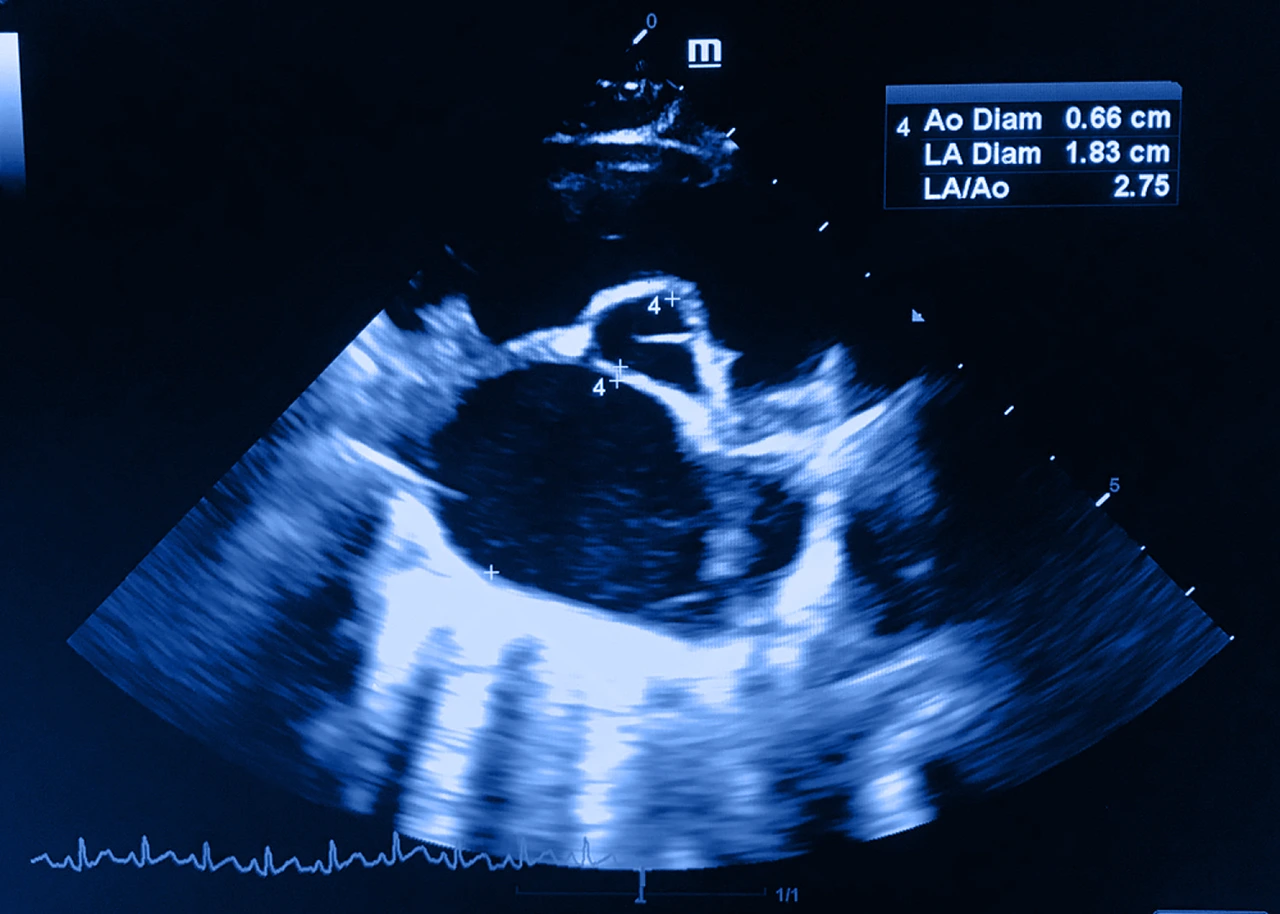

• Ecocardiograma: es el estudio más importante para confirmar la enfermedad permite:

• Medir el grosor del músculo cardiaco.

• Evaluar si existe obstrucción del flujo sanguíneo.

• Analizar la válvula mitral.

• Ver el movimiento del tabique interventricular.

• Es la prueba fundamental tanto para diagnóstico como para seguimiento.

Ecocardiograma para diagnosticar la presencia de miocardiopatía hipertrófica en un paciente.